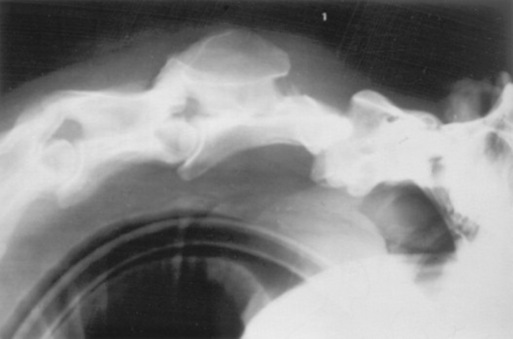

A complete myelographic examination should include neutral and stressed (flexed and extended) views of the cervical vertebrae.1863,1883 Horses with dynamic spinal cord compression show obliteration of the dorsal and ventral contrast columns during ventroflexion of the neck (Fig. 35-29), whereas spinal cord compression is not apparent with the neck in the neutral position. Static vertebral canal stenosis is characterized by constant spinal cord compression regardless of cervical position (Fig. 35-30). In some cases of static compression, ventroflexion of the neck stretches the ligamentum flavum and relieves spinal cord compression, whereas hyperextension exacerbates compression. In horses with obvious sites of spinal cord compression on neutral myelographic views, excessive flexion and extension of the neck should be avoided while obtaining dynamic views to prevent exacerbation of spinal cord injury.

Fig. 35-29 Myelographic examination of C3 through C6 with the cervical spine in ventroflexion. Dynamic instability and spinal cord compression are present at the C3-C4 and C5-C6 articulations. The ventral contrast columns are obliterated, and the dorsal contrast columns are narrowed (to less than 2 mm) at C3-C4 and C5-C6 (arrows).